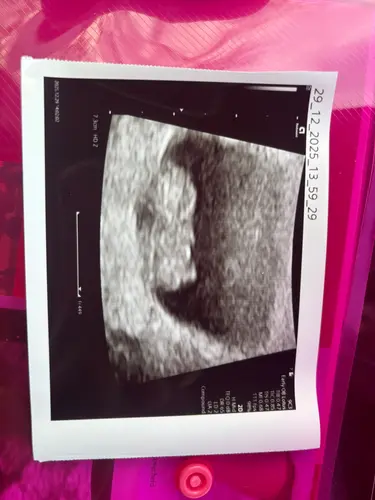

Gister mijn 2e echo gehad. 8 weken 6 dagen, dus nu de 9 aangetikt. De kleine bewoog al lekker door het vruchtwater en een mooi kloppend hartje 😍 over 2 weekjes de termijnecho